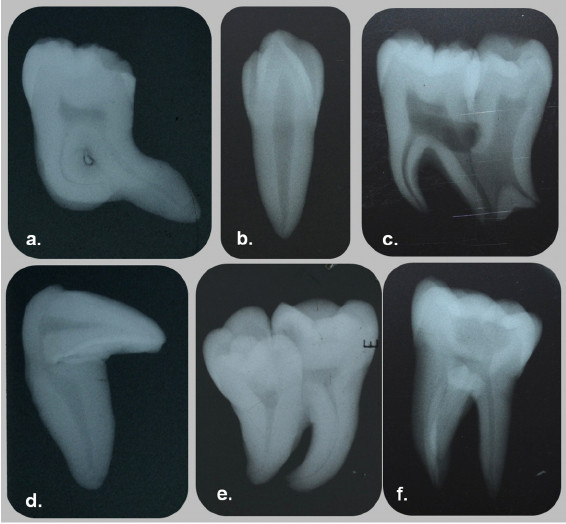

A brief mention will be made of yet another positional anomaly of the canines: transmigration. Transmigration is exclusive of the mandibular perma- nent canine. In this anomaly, the canine from one side of the arch migrates through the bone and erupts on the opposite side of the arch. For instance, the right mandibular canine migrates through the sympheseal area and erupts into the arch in the place where the left canine usually erupts. This anomaly could present a complex clinical problem, because the clinician will be facing a situation where the canine from one side appears to be missing, while the opposite side may appear to have a supernumerary canine.15 Like so many dental problems, this last anomaly is best detected by radiographic examination. If detected early enough, its treatment may not be too difficult. This will reinforce the urging of a mature teacher to obtain and examine our patients’ records with care and attention to detail.